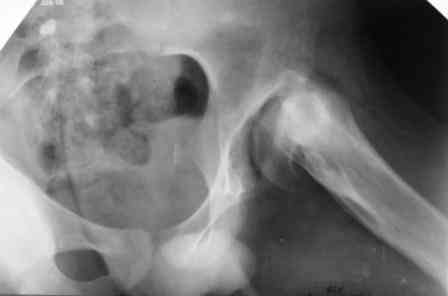

дисплазия тазобедренного сустава

Больному 16 лет, болеет с рождения.Оперирован в детстве( корригируюшая межвертельная остеотомия с фиксацией пластиной), три года назад удалии пластину. Обратился к нам, выраженно хромота, укорочение бедра на 4 см, ходит безболезненно, отведение ограниченно при отведении и ротации. Буду рад вашим предложениям.